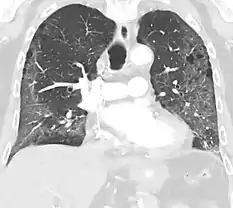

Crazy paving

The crazy paving pattern may occur when there is both interlobular and intralobular widening. This sometimes resembles a road paved with irregular bricks or tiles. It is typically diffuse, involving larger areas of one or multiple lobes. There are a variety of potential causes, including Pneumocystis pneumonia, late-stage adenocarcinoma, pulmonary edema, some types of idiopathic interstitial pneumonias, diffuse alveolar hemorrhage, sarcoidosis, and pulmonary alveolar proteinosis.[6] COVID-19 has also been shown to occasionally cause GGOs with a crazy paving pattern.[11]